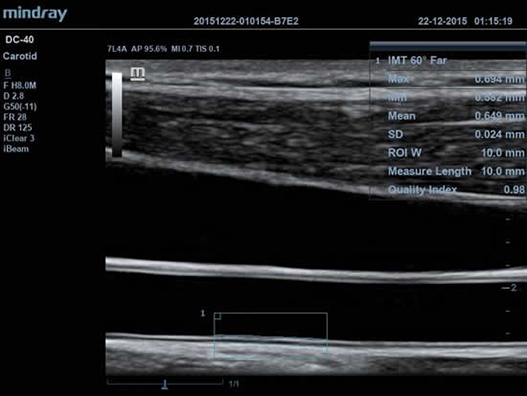

• Функция Auto IMT автоматически измеряет толщину комплекса интима-медиа.

• Auto IMT Package – измерения и анализ толщины комплекса интимамедии (КИМ) сонной артерии;